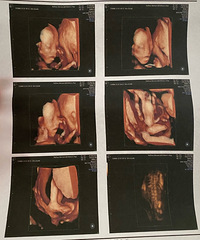

预产期:2022.08.30建卡医院:台州妇女儿童医院产检医院:台州妇女儿童医院胎宝宝小名:未定生产医院:台州妇女儿童医院B超照片/孕期相关照片一张:

预产期:2022年4月10日建卡医院:椒江妇幼保健所产检医院:椒江妇幼保健所胎宝宝小名:崽生产医院:台州妇女儿童医院或路桥恩泽医院B超照片/孕期相关照

预产期:2022/2/20建卡医院:路桥路北卫生院产检医院:椒江妇幼保健所胎宝宝小名:肉肉生产医院:考虑妇女儿童医院,台州市中心医院,第一张B超照片:

预产期:2021.11.8建卡医院:台州妇女儿童医院产检医院:台州妇女儿童医院胎宝宝小名:未起生产医院:台州妇女儿童医院B超照片/孕期相关照片一张:

预产期:2021.2.13建卡医院:台州医院产检医院:台州医院胎宝宝小名:由由/小丸子/绵绵/boly生产医院:看情况吧B超照片/孕期相关照片一张:

预产期:2021年4月19日(提前3月10日生)建卡医院:桐屿卫生院产检医院:恩泽宝宝小名:牛小壮生产医院:恩泽B超照片/孕期相关照片一张:

预产期:2022.2.4建卡医院:临海邵家渡卫生院产检医院:恩泽妇产+临海妇幼保健院胎宝宝小名:lucky生产医院:预计台州医院新院B超照片/孕期相关照片一